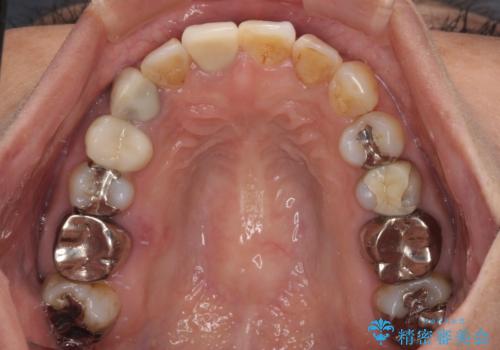

- 上下前歯のデコボコを気にして来院された患者様です。

歯列としては、ワイヤー装置でもインビザラインでも、どちらでも対応可能でしたが、処置されている歯が多く、ワイヤー装置を装着するためには処置歯のやり直しが必要な状態でした。

インビザラインでもアタッチメントを装着できないという同様のデメリットがありますが、比較的矯正治療を行いやすい歯列であったので、インビザラインによる矯正治療を行うこととしました。